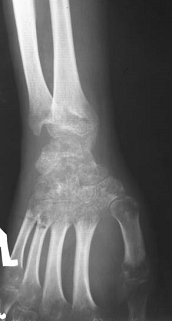

Рис.7.

Пятнистый остеопороз костей кисти (синдром Зудека).